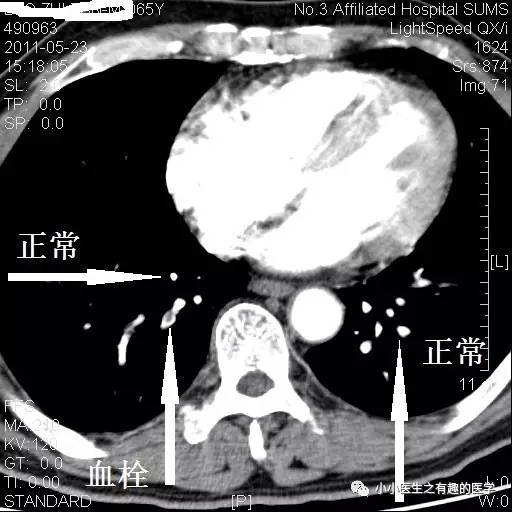

看看下图,这才是正常的肺动脉。

再复习一下,肺动脉乃人字形。